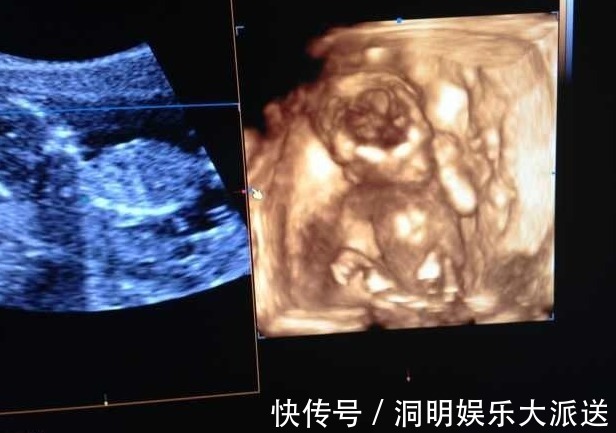

由于她的年纪小,怀孕后她并不知道,所以等到快三个月的时候她才反应过来,于是她要去做产检也是在怀孕3个月后去的。而第一次产检她婆婆就陪着她去,也怕她不懂所以陪着去,等到了医院后,医生就开始问了很多问题,因为医生想要了解孕妇的健康情况,也要根据这些情况来判断孕妇未来的一个生产方式等等!

一般一些丰富经验的医生就会问的比较细致,而且还会有一些很尴尬的问题。于是有的医生也会先把家人支开再问,避免引起不必要的事端。而洁儿运气也好,这个医生也是把她婆婆支开了,于是问他有没有做过流产,洁儿一听非常尴尬,脸瞬间就红了,然后她也如实的回答了,说有过一次!果不其然,像这样有经验的医生可能早就猜到了。其实她婆婆心里也明白,事后也一直想套话,但是洁儿也知道婆婆想知道,也没有被套话。